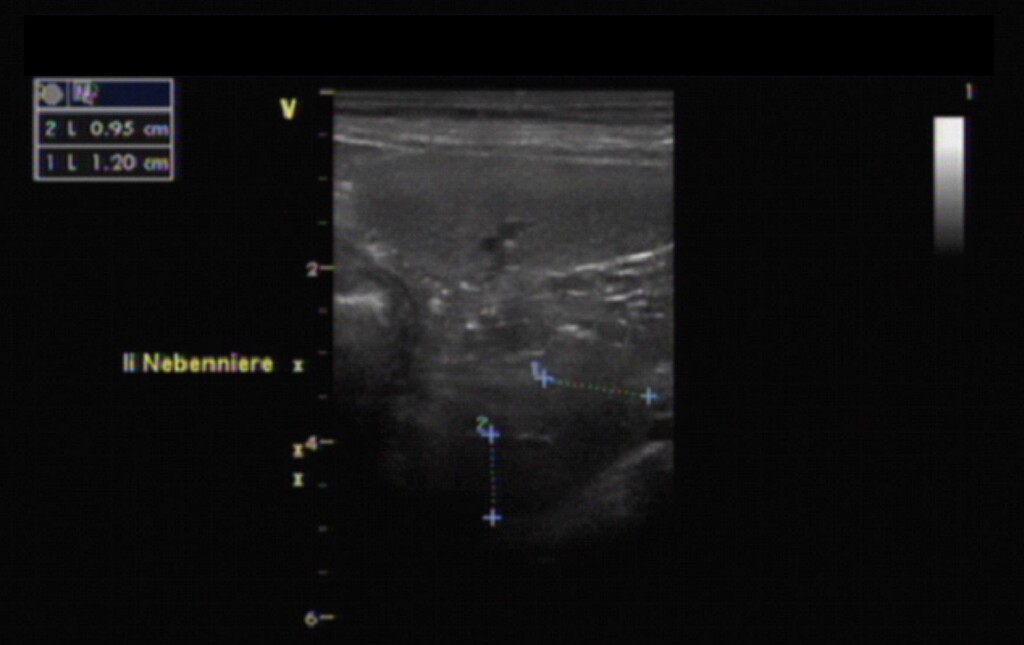

Morbus Cushing oder „Hyperadrenokortizismus“ beschreibt eine Überfunktion der Nebennierenrinde. Diese kann verursacht werden durch einen kleinen Tumor in der Hirnanhangsdrüse, welcher die Nebennieren permanent dazu stimuliert, Kortisol zu bilden. Die Folge ist ein Wachstum beider Nebennieren. Ebenfalls möglich ist, dass sich in einer der beiden Nebennieren ein Tumor bildet, der eigenständig Kortisol produziert. Hierdurch wird die andere Nebenniere kleiner, da sie kein Kortisol mehr produzieren muss.

2. Ultraschalluntersuchung der Nebennieren